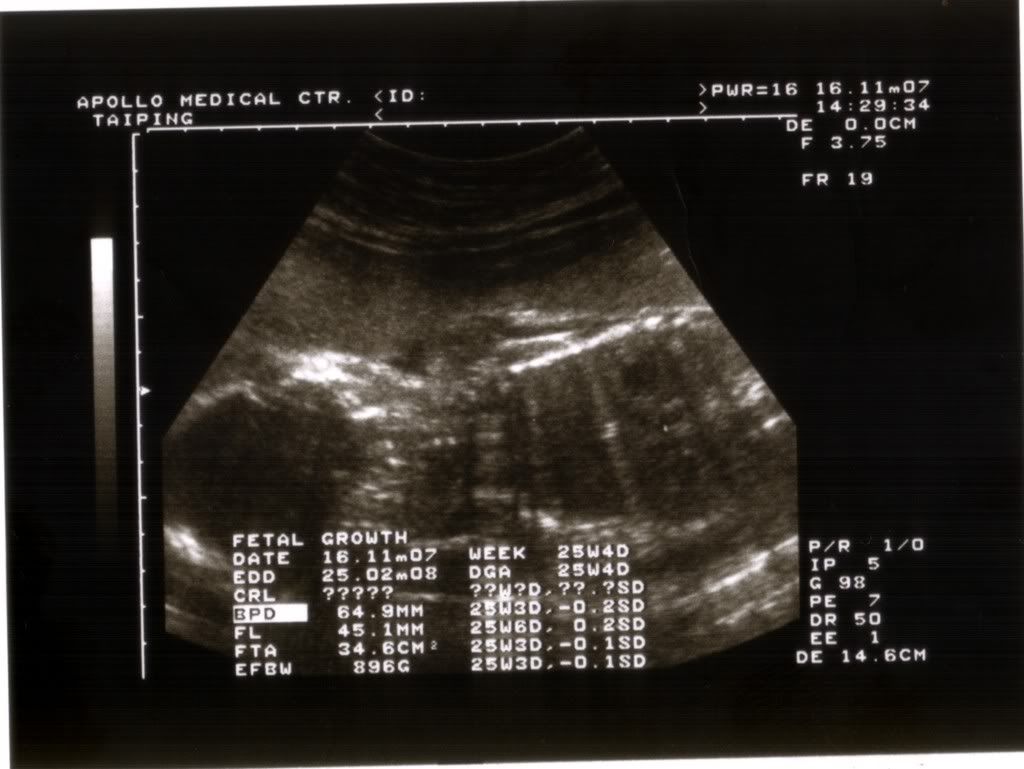

EFBW 就是宝宝预测的体重。。没错。。